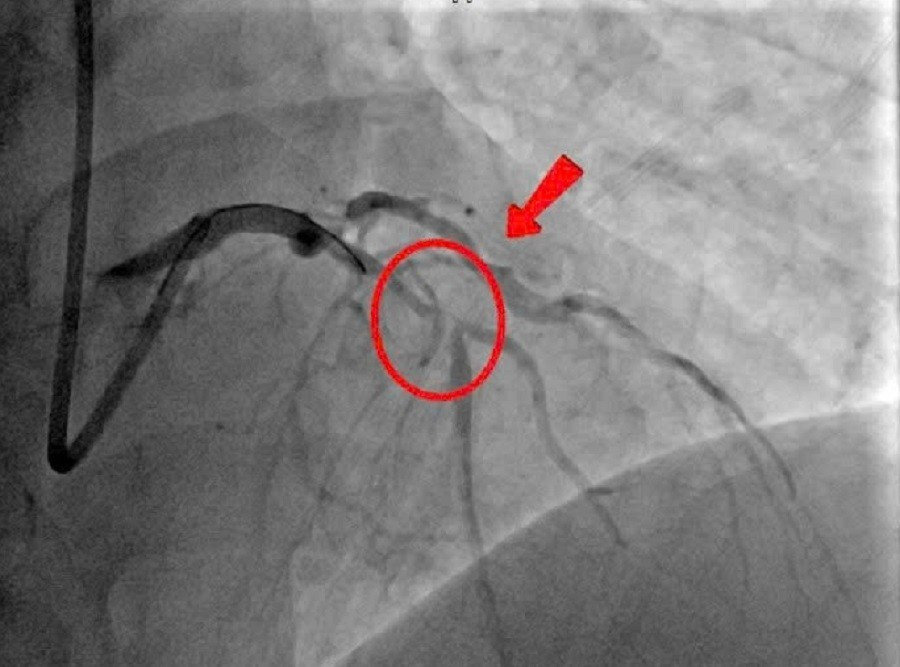

Vị trí mạch máu bị tắc nghẽn trên hình ảnh chụp mạch vành cấp cứu được bác sĩ ghi nhận.

Ngay sau khi phát hiện cơn nhồi máu cơ tim cấp đang đe dọa tính mạng người bệnh, ê kíp các bác sĩ tim mạch đã khẩn trương hội chẩn và quyết định chụp mạch vành cấp cứu. Hình ảnh cho thấy đoạn gần nhánh liên thất trước – vị trí then chốt trong việc cung cấp máu cho cơ tim bị hẹp rất nặng.